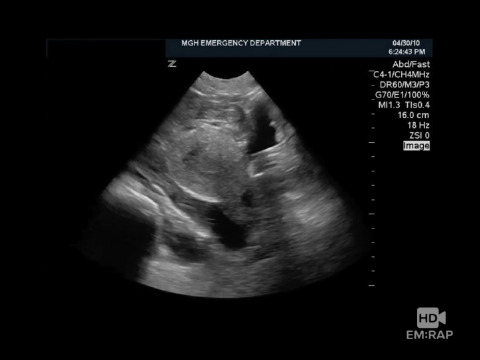

Pelvic Ultrasound in Vaginal Bleeding

Dr. Vicki Noble reviews how to perform a transabdminal vaginal ultrasound and the key findings to look for an IUP, free fluid, and ectopic pregnancies.